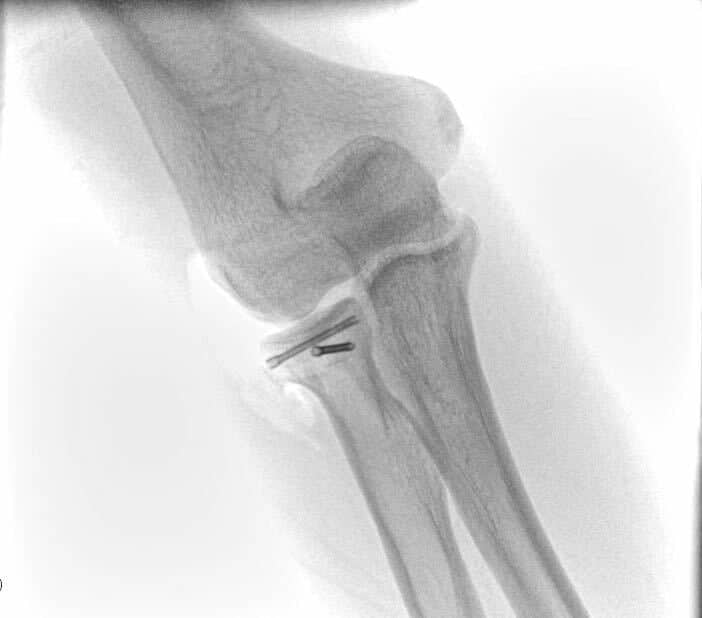

The elbow joint consists of 3 bones: the humerus (arm bone), ulna and radius (forearm bones). These bones are held together by multiple muscles, tendons and ligaments and work in unison in a hinge joint that bends your elbow, but also controls rotation of your forearm and hand. A complex elbow injury is often times referred to as the “terrible triad” of the elbow. This type of injury includes an elbow dislocation, a radial head fracture and a coronoid process fracture, together with various degrees of associated ligamentous injury.

Complex elbow fractures are usually suspected based on the mechanism of injury and associated symptoms and confirmed by simple x-rays. Your doctor may request a CT scan of the elbow, to aid with preoperative planning.

An elbow fracture-dislocation should get treatment as soon as possible. A dislocated elbow should be set back in place under sedation. This usually happens in the emergency department. A repeat x-ray will confirm that your elbow is in a congruent – acceptable position. After this happen, you will be typically referred to an orthopaedic surgeon for definitive treatment. Surgery usually involves the following:

- Fixation or arthroplasty of the radial head

- Fixation or suture fixation of the coronoid or anterior capsule

- Distal humerus fracture fixation, if present

- Repair of torn ligaments (LUCL +/- MCL) with suture anchors

- Olecranon fracture fixation, if present

Most terrible triad injuries require surgical management to restore the functionality of your elbow. Surgery involves addressing all the injury components in your elbow. These may include fixation or replacement of the radial head, fixation or suturing of the coronoid and repair of the avulsed ligaments of your elbow.